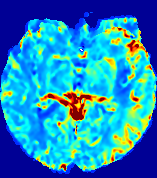

LesionRefer to captionRefer to captionRefer to captionRefer to captionRefer to captionRefer to caption𝐕rgbsubscript𝐕𝑟𝑔𝑏{\bf{V}}_{rgb}Refer to captionRefer to captionRefer to captionRefer to captionRefer to captionRefer to caption𝐕2subscriptnorm𝐕2{\|\bf{V}}\|_{2}Refer to captionRefer to captionRefer to captionRefer to captionRefer to captionRefer to captionRefer to caption3.53.53.52.82.82.82.12.12.11.41.41.40.70.70.70.00.00.0(mm/s)𝑚𝑚𝑠(mm/s)D𝐷DRefer to captionRefer to captionRefer to captionRefer to captionRefer to captionRefer to captionRefer to caption0.0200.0200.0200.0160.0160.0160.0120.0120.0120.0080.0080.0080.0040.0040.0040.0000.0000.000(mm2/s)𝑚superscript𝑚2𝑠(mm^{2}/s)Slice #1Slice #2Slice #3Slice #4Slice #5Slice #6

Figure 3: PIANO feature maps for one stroke patient, where the lesion is located in the left hemisphere. Top row: segmented stroke lesion region (white) on different slices, obtained from ISLES 2017. The corresponding slices for the PIANO feature maps are shown in the following rows.

For a better insight into an estimated velocity field 𝐕𝐕{\bf{V}} and diffusion field 𝐃𝐃{\bf{D}}, we compute the following maps: (1) 𝐕rgbsubscript𝐕𝑟𝑔𝑏{\bf{V}}_{rgb}: Color-coded orientation map of 𝐕=(Vx,Vy,Vz)T𝐕superscriptsuperscript𝑉𝑥superscript𝑉𝑦superscript𝑉𝑧𝑇{\bf{V}}=(V^{x},V^{y},V^{z})^{T}, obtained by normalizing 𝐕𝐕{\bf{V}} to unit length and mapping its 3 components to red, green, blue respectively; (2) 𝐕2subscriptnorm𝐕2\|{\bf{V}}\|_{2}: 222 norm of 𝐕𝐕{\bf{V}}; (3) D𝐷D: scalar field in Eq. 5.

Fig. 3 and Fig. 4 show the PIANO feature maps estimated from two ISLES 2017 patients: all are highly consistent with the lesion in both cases. Details of the blood flow trajectories are revealed in 𝐕rgbsubscript𝐕𝑟𝑔𝑏{\bf{V}}_{rgb} by the ridged patterns and the sharp changes of colors in the unaffected (right) hemisphere, while the flat patterns appearing within the lesion provide little directional information about the velocity and indicate low velocity magnitudes. Velocity magnitudes are more directly visualized via 𝐕2subscriptnorm𝐕2\|{\bf{V}}\|_{2}, from which one can easily locate the lesion where 𝐕2subscriptnorm𝐕2\|{\bf{V}}\|_{2} is low. D𝐷D also indicates lower diffusion values in the lesion, though with less contrast potentially due to the fact that it captures the accumulated effect of CA diffusion at the voxel-level.